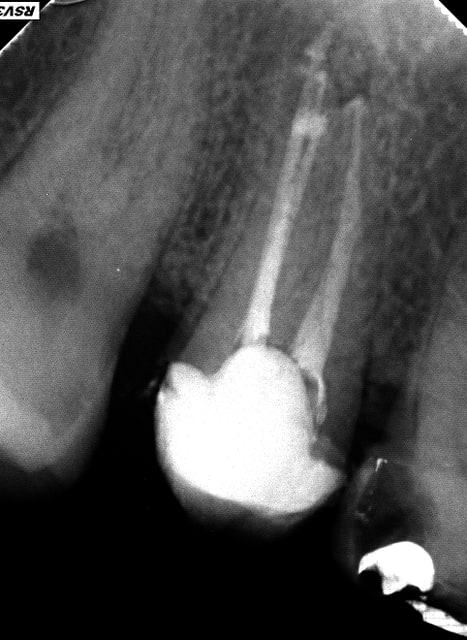

Je m'entraine au mac spaden mais abrès avoir réalisé des bouchons apicaux au friendo ( enfin j'essaye par ce que ca bloque un peu trop loin de l'apex vu que je n'ai pas toutes les tailles d'inserts lol !); Pas franchement de meilleure image qu'au monocone scellé.

Je me fais chier pour rien je pense mais j'appréhende cet engin qui tourne à 40 000 tours ( j'utilise le diametre 40 pour une préparation au R25)

Ca compacte dur par contre vu que l'intégralité du cone ( ici un diametre 40) disparait dans le canal.

En termo-compaction pure à combien de mm de l'apex faut il envoyer l'engin ? vu la pression que ca développe une connerie est vite arrivée.

pas cool de commencer par une 36 de 4 canaux. Par contre.)))))))

R1 iqqn0y - Eugenol

R2 sxl3pa - Eugenol

R3 ulnhut - Eugenol

R4 hefdnh - Eugenol

Loop trrma6 - Eugenol

En thermocompaction faut se tenir à 4mm de l'apex (a peu pres). Et même si on voit pas tout le temps la différence radiologiquement avec le monocone, on est sur que c'est étanche à l'apex (ce qui est pas du tout le cas avec un monocone scellé...)

PS: belle obtu ;)

Oui c'est la meme chose avec le système B utilisé (friendo de hufriedy). Seulement j'ai pas réussi à descendre les inserts à 4 mm de l'apex (trop gros taille FM/06) curieux d'ailleurs dans certains canaux je n'en suis pas loin. Mon obturation est donc en monocone scellé au bout.)))))

Pour un alésage en 25 /06 quel diametre utiliser ?

Un compacteur de 30. Les revo condensor sont parfait ils ont une bague violette. Je ne me sers presque que de ces thermocompacteurs. La densité des cônes compactes à la radio dépend de leur concentration en eugenol.donc peu significatif. Pour me faire la main je passais le cone puis un.coup de finger spreader et après seulement le compacteur